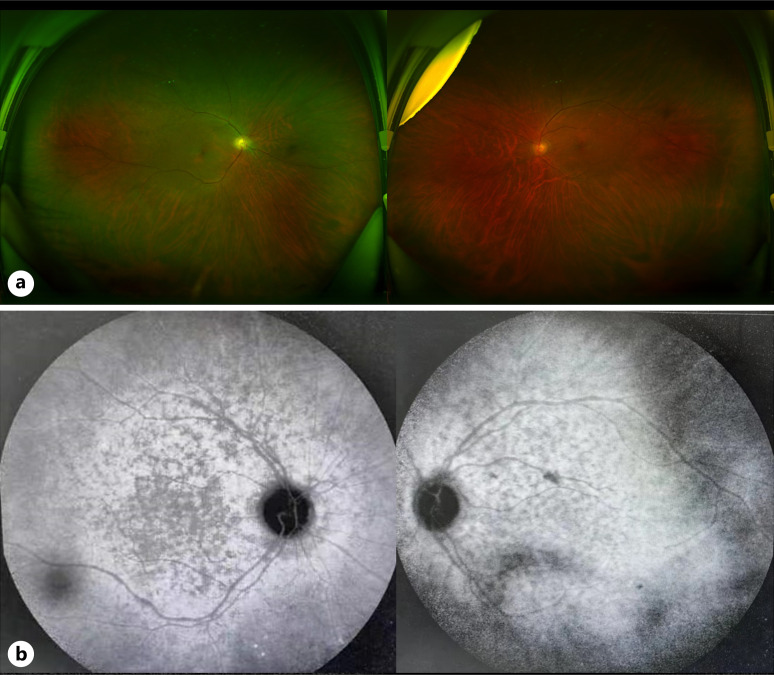

Case presentation: This report details a case of a patient who initially presented with night blindness and visual field defects as the primary symptoms. Through a comprehensive and systematic examination process, which involved detailed ophthalmological examinations and multidisciplinary diagnostic approaches, esophageal, and cardia MM was ultimately diagnosed. The patient was referred to an external hospital for comprehensive antitumor management, and posttreatment, the patient self-reported a notable improvement compared to the pretreatment state.